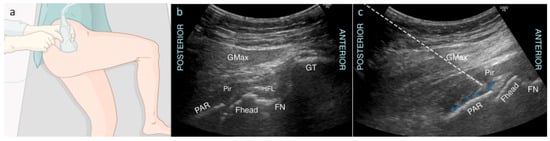

Vermeylen et al. from Turnhout, Belgium, developed a new ultrasound-guided technique to block the nerves to the posterior capsule called the posterior pericapsular deep-gluteal (PPD) block [48]. The block is performed with the patient positioned in the lateral decubitus position with both their knee and hip flexed at 90 degrees (Figure 7a). A low-frequency curved probe is placed on the greater trochanter and aligned parallel with the long femoral axis. The probe is then moved slightly dorsal to visualize the bony landmarks: the greater trochanter, the femoral neck and head, and the posterior acetabular rim (Figure 7b) [48]. Superficial to the bony landmarks, the piriformis muscle is identified, deep to the gluteus maximus muscle. The needle is introduced in-plane from lateral to medial until the tip contacts the posterior acetabular rim near the attachment of the ischiofemoral ligament. After negative aspiration, 20 mL of local anesthetic is injected with fluid spread over the posterior acetabular rim, the posterior hip capsule, and under the piriformis muscle (Figure 7c) [48]. With this volume, the superior gluteal nerve and the nerve to the quadratus femoris muscle is expected to be covered.

Figure 7. (a) Position of the patient during the posterior pericapsular deep-gluteal block. The ultrasound probe and needle are in line with the axis of the femur, with in-plane needle puncture from the posterior aspect. (b) Corresponding ultrasound image showing the gluteal muscles covering the bony landmarks: Fhead, femoral head; FN, femoral neck; GMax, gluteus maximus; GT, greater trochanter; IFL, ischiofemoral ligament as part of the posterior hip capsule; PAR, posterior acetabular rim; Pir, piriformis muscle. (c) Ultrasound image of the needle trajectory. Dashed line: needle trajectory; Blue arrows: spread of local anesthetic over the posterior acetabular rim and posterior hip capsule, deep to the piriformis muscle. Reproduced with permission from Vermeylen K et al., BJA Open; published by Elsevier, 2023 [48].